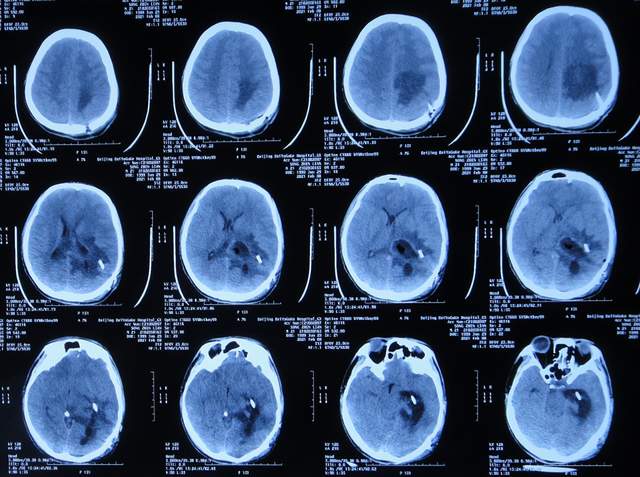

入院后5天即2021年1月18日,查头颅CT增强示颅内占位(图-4)。

图-4:2021年1月18日头颅CT增强